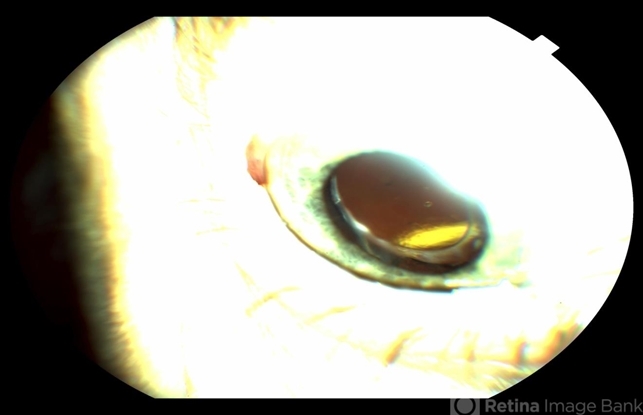

- Iluvien (Fluocinolone Acetonide Intravitreal Implant) for Diabetic Macular Edema

- slit lamp photo, fluocinolone implant

- Photo slit lamp biomicroscope

- Slit lamp photograph displaying Iluvien (fluocinolone acetonide intravitreal implant).